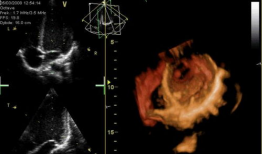

心脏跳动的视频,揭秘心脏跳动的奥秘

你知道吗?最近在网上流传着一个特别神奇的视频,它记录了心脏跳动的瞬间。这可不是普通的视频,它让我们仿佛能感受到心跳的力量,那种感...